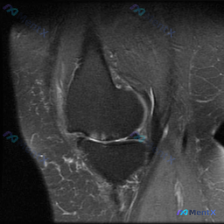

膝关节MRI看到半月板高信号+镜像骨髓水肿,这个病例你会怎么诊断?

整理了这张单膝关节冠状位T2加权脂肪抑制MRI,跟大家分享一下读片思路

这是一张膝关节冠状位T2加权脂肪抑制序列MRI,图像对比度良好,能够清晰显示关节内软组织结构;左侧为膝关节外侧,右侧为内侧,本次显示层面包含股骨外侧髁、胫骨外侧平台及外侧关节间隙。

- 外侧半月板:体部/后角区域可见异常高信号影,斜行或水平穿过半月板低信号实质,延伸至关节面边缘,符合半月板撕裂的典型影像学表现

- 骨骼信号:股骨外侧髁、胫骨外侧平台的关节面下都可见局灶性T2高信号,边缘模糊,提示骨髓水肿(骨挫伤),正好是股骨和胫骨对应的「镜像」位置

- 关节相关改变:外侧关节间隙软骨轮廓欠规整,关节腔内可见少量液体信号,提示少量关节积液;外侧关节间隙有轻微狭窄倾向,周围软组织可见少量渗出